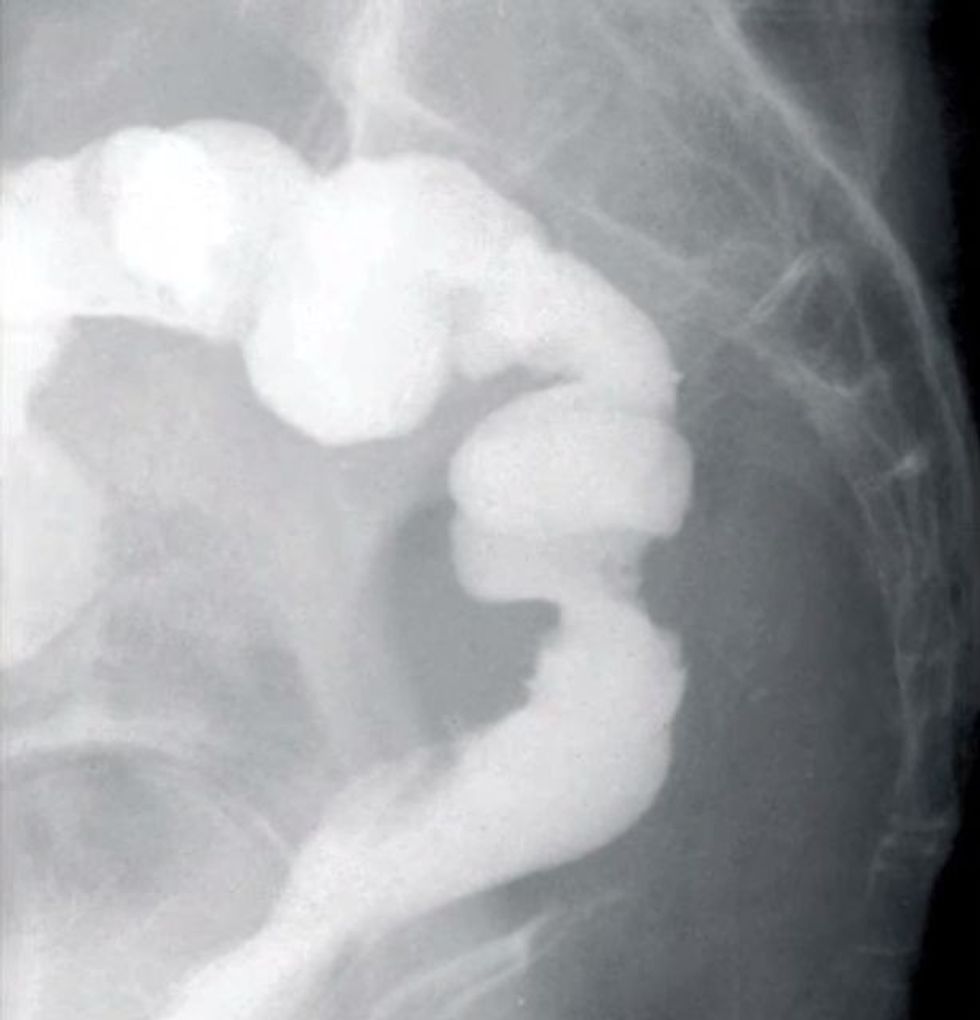

Jasminka Vellkoska vazhdon të paguaj çmimin e gabimit mjekësor. Ajo flet pas tre vitesh për herë të parë për rastin e saj kur mjekët ia ngjitën gabimisht vagjinën me zorën e trashë gjatë një operacionit për largimin e kancerit në abdomen, përcjell Telegrafi Maqedoni.

Dailymail.co.uk shkruan ''E mbijetuara nga kanceri i nxjerr gazrat nga vagjina pasi mjekët gabimish ia kanë ngjitur atë me zorën e trashë''Rastin e kanë komentuar edhe disa ekspertë të kirurgjisë që kanë edhe blogjet e tyre, duke e klasifikuar si marrëzi dhe pa kujdes që bie ndesh me principet e profesionit.